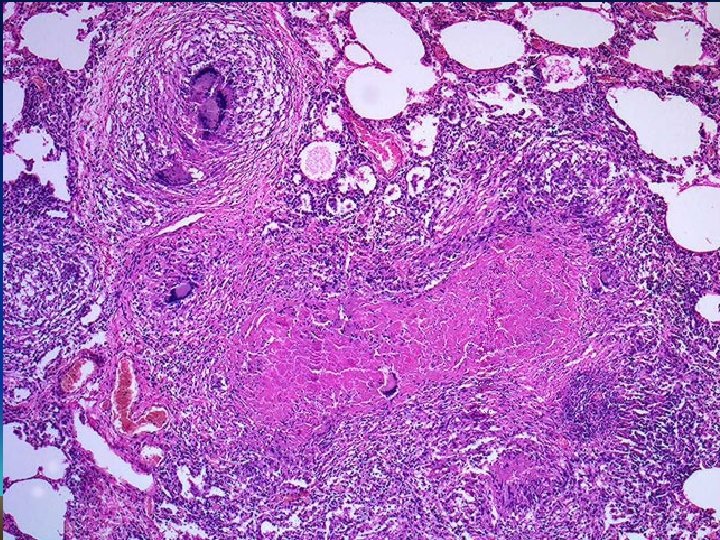

Histology : Epithelioid cell granulomas • epithelioid cells • lymphocytes • plasma cells • multinucleated langhan’s type giant cells • with or without central caseation

Granulomatous Inflammation • Clusters of T cell-activated macrophages, which engulf and surround indigestible foreign bodies (mycobacteria, H. capsulatum, silica, suture material) • Resemble squamous cells, therefore called “epithelioid” granulomas

Granulomatous inflammation Granulomas are millimeter size nodules of chronic inflammatory cells that can be isolated or confluent. Granuloma formation is the result of dealing with indigestible substances or pathogens and walls them off The essential component are modified macrophages named epithelioid cell (because of shape). Epithelioid cells can form multinucleated giant cells. Epithelioid cells are surrounded by a collar of lymphocytes and occasionally plasma cells. Fibrous connective tissue often surrounds granulomas (remodeling of tissue) Areas within the granuloma can undergo necrosis (prototype: caseous necrosis in tuberculosis). Necrosis can lead to calcification or liquefaction and formation of a cavern if drained.